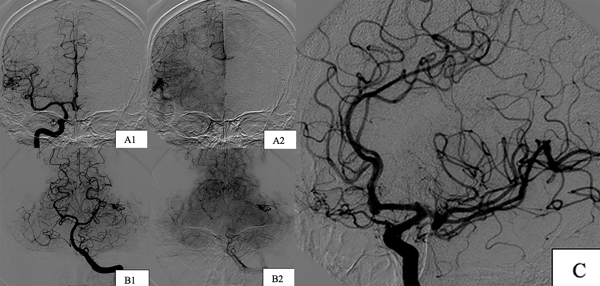

Paciente de sexo masculino, de 41 años de edad al cual se le diagnosticaron dos MAVs cerebrales de forma incidental, una supratentorial (temporal derecha), con aferencias de rama silviana y drenaje venoso precoz al seno sigmoideo homolateral y otra infratentorial (cerebelosa superior izquierda) con aferencias de la arteria cerebelosa superior homolateral y drenaje precoz hacia el seno sigmoideo homolateral, asociadas a la presencia de un aneurisma de bifurcación carotídea izquierda (Figura 2), dichas lesiones se identificaron en contexto de estudio del ROWS, con el cual había sido diagnosticado desde los 11 años.

Figura 2. Imágenes preoperatorias caso 1. A) MAV temporal derecha. A1) Incidencia frente aferencias. A2) Incidencia frente drenaje venoso. B) MAV cerebelosa superior izquierda. B1) Incidencia frente aferencias. B2) Incidencia frente drenaje venoso. C) Aneurisma de bifurcación carotídea izquierdo incidencia oblicua.